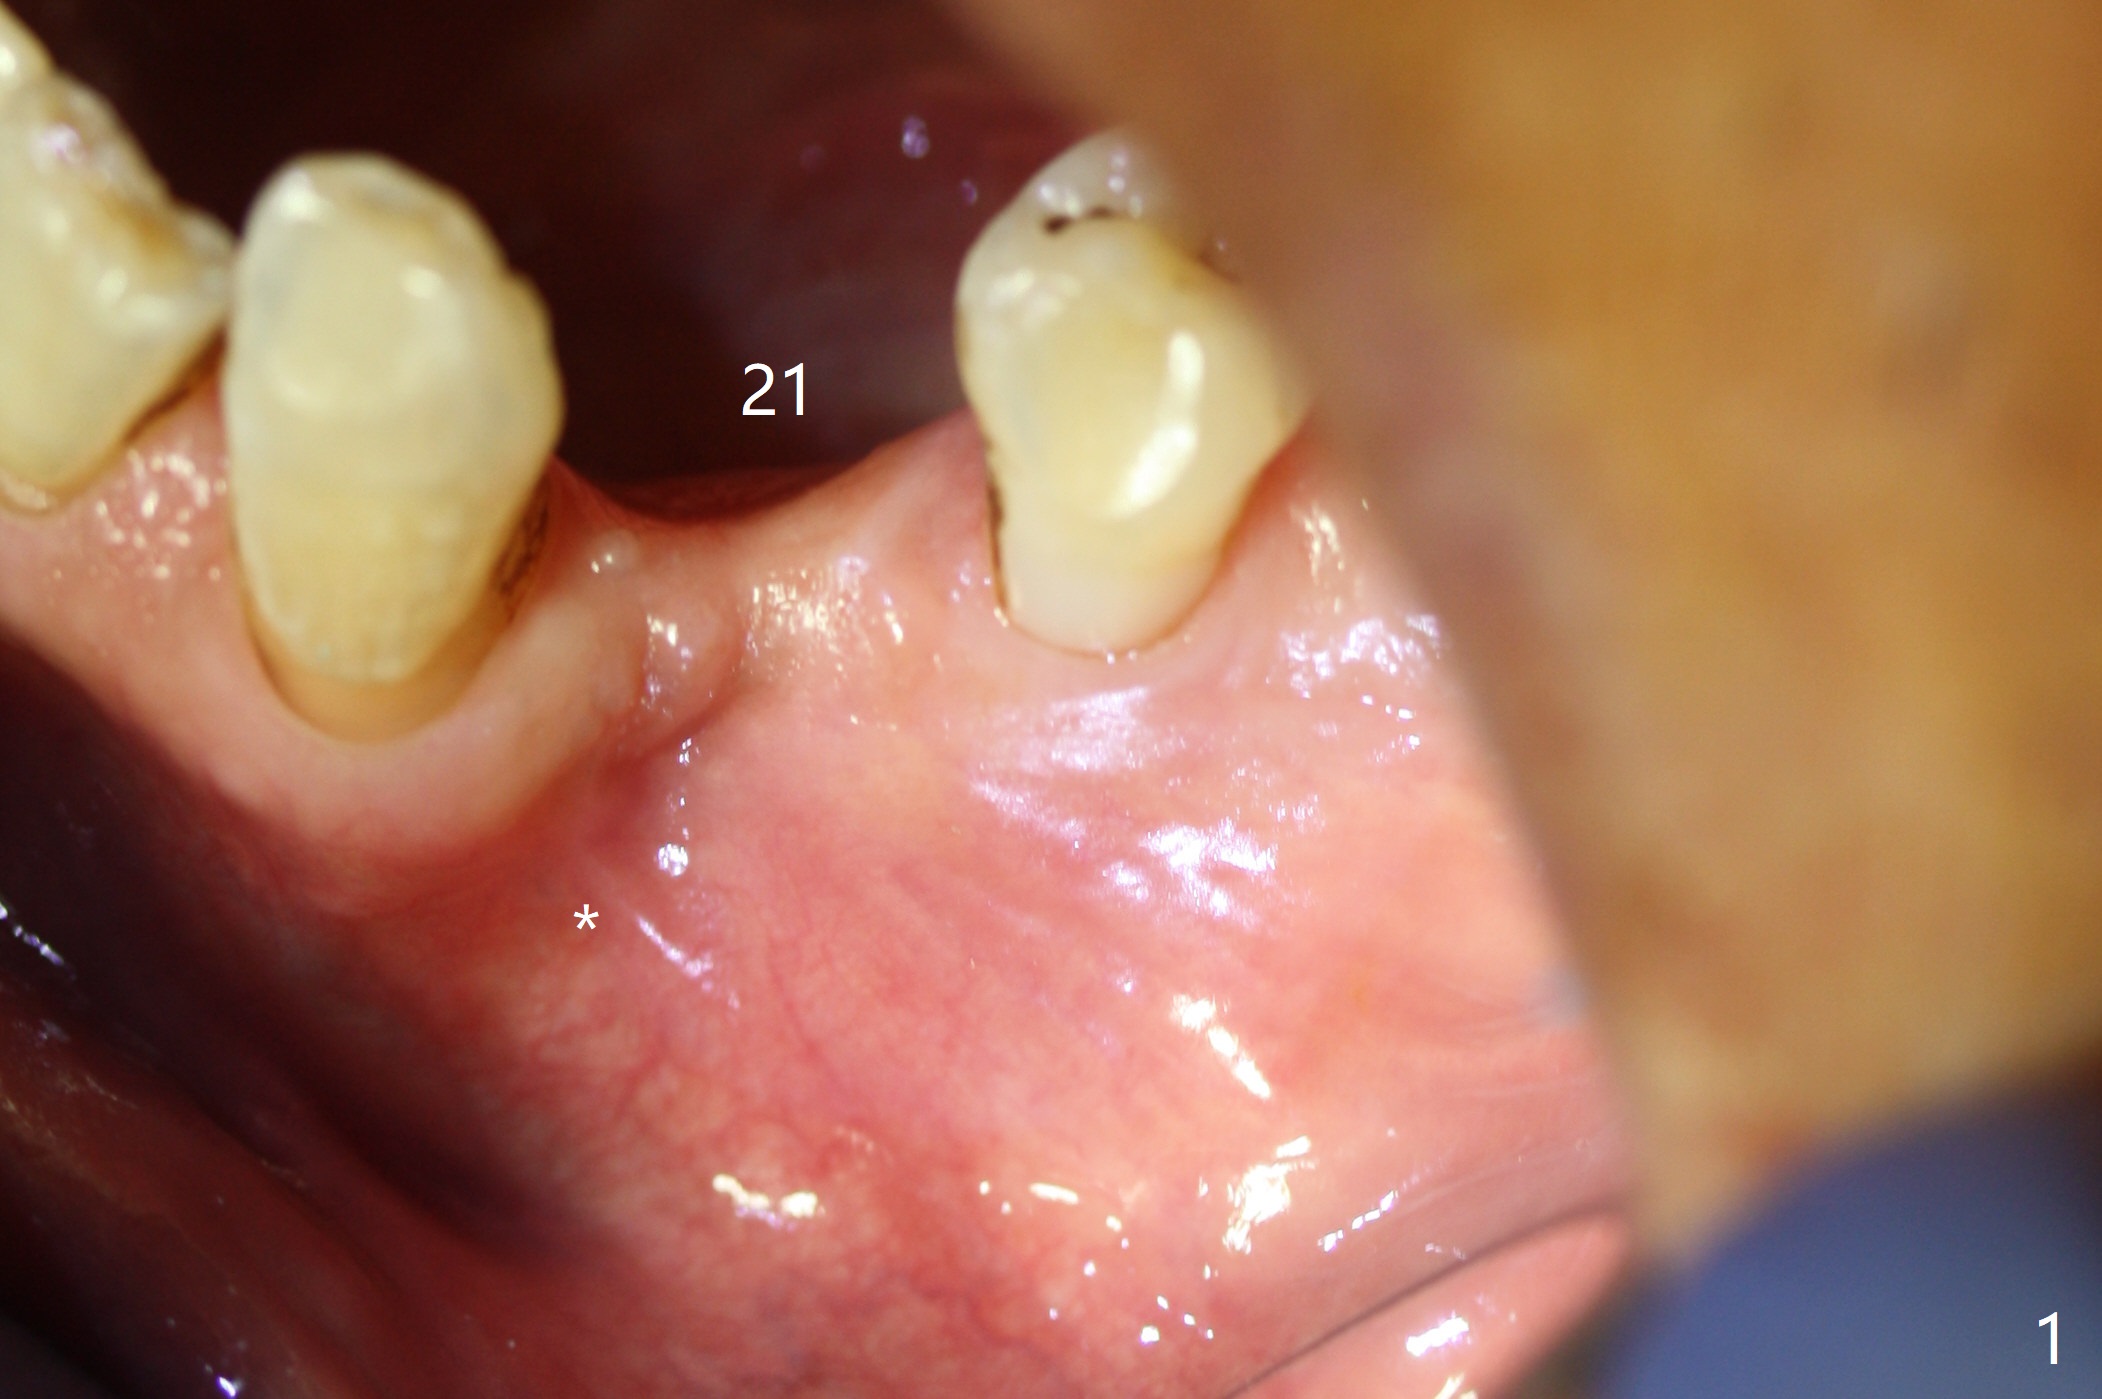

After incision at #21 (Fig.1) and flap elevation, the narrow ridge is reduced and initial osteotomy is made (Fig.2,3). Following moving the osteotomy distal, a 3x12(4) mm 1-piece implant is placed with >35 Ncm (Fig.4-6). Vanilla Graft is placed in the most concave buccal defect (Fig.1,4 *) and over the ridge reduction area (Fig.6 *). No bone loss is observed 3 months postop (Fig.7).